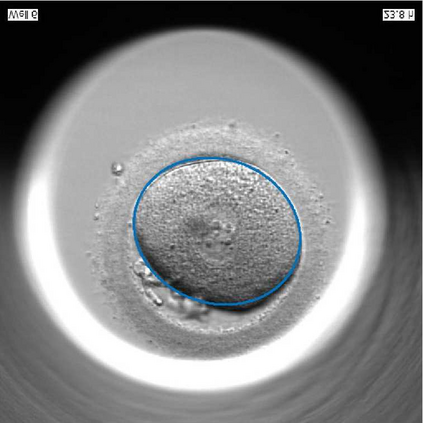

We present a novel method for identification of the boundary of embryonic cells (blastomeres) in Hoffman Modulation Contrast (HMC) microscopic images that are taken between day one to day three. Identification of boundaries of blastomeres is a challenging task, especially in the cases containing four or more cells. This is because these cells are bundled up tightly inside an embryo's membrane and any 2D image projection of such 3D embryo includes cell overlaps, occlusions, and projection ambiguities. Moreover, human embryos include fragmentation, which does not conform to any specific patterns or shape. Here we developed a model-based iterative approach, in which blastomeres are modeled as ellipses that conform to the local image features, such as edges and normals. In an iterative process, each image feature contributes only to one candidate and is removed upon being associated to a model candidate. We have tested the proposed algorithm on an image dataset comprising of 468 human embryos obtained from different sources. An overall Precision, Sensitivity and Overall Quality (OQ) of 92%, 88% and 83% are achieved.